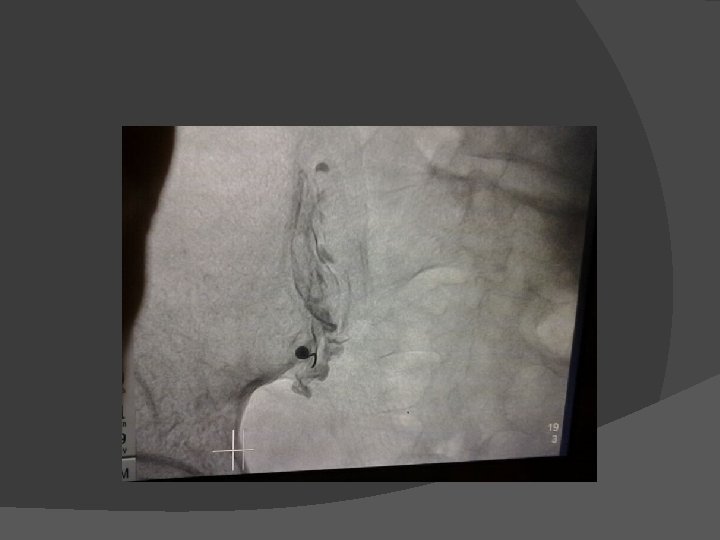

� Kasus 1 Laki-laki, 60 th, mengeluh nyeri selama 10 tahun di wajah sisi kanan, hilang timbul seperti tersengat listrik. DM (+), HT(+), mendapat terapi carbamazepin dan pregabalin namun nyeri berkurang hanya sedikit. TRIGEMINAL GANGLION RADIOFREQUENCY